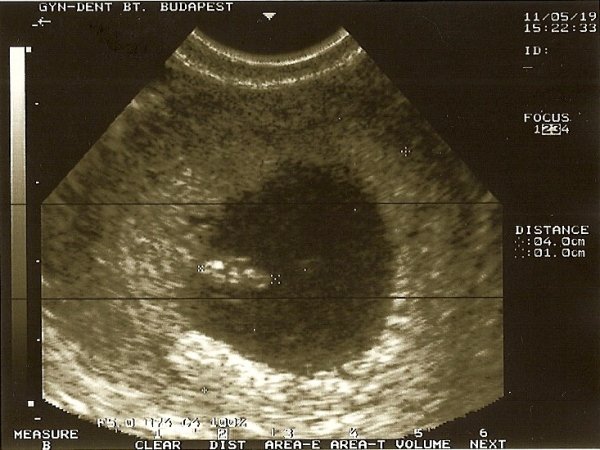

Dokinál minden rendben volt. Kaptam képet, és láttam, ahogy ver a pici szívecskéje!

1dm egyébként a baba.